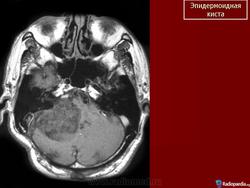

С 1985 по 2000 г.г. в НИИ нейрохирургии им. Н.Н. Бурденко обследовано и оперировано 78 больных с эпидермоидными кистами задней черепной ямки. Изучен клинический симптомокомплекс и КТ, МРТ картина эпидермоидных кист задней черепной ямки.

Качество оперативного лечения оценивалось изучением динамики неврологического статуса, данных КТ, МРТ, как до операции, так и после операции на разных его стадиях. Современные радиологические исследования и микрохирургическая техника полностью обеспечивает радикальное удаление эпидермоидных кист с хорошим после операционным результатом.

Эпидермоидная киста.